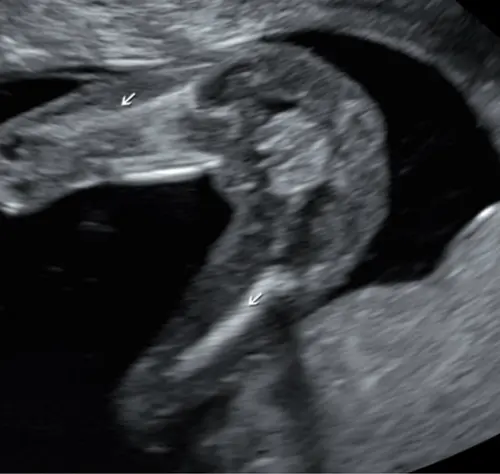

Foto鈥檚 zijn overigens van echo die gemaakt is met 13 + 5

Ik zie dus helemaal niets bij niemand haha! Iemand die bij mijn echo iets ziet?

Bij ons zag je duidelijk iets tussen zijn beentjes zitten met 13.1 weken en dat zie ik hier niet wij krijgen een jongetje..

Buiten een erg lief wipneusje is dit een jongetje 馃挋

Ik denk (d茅nk) het omdat ik geen witte streep/strepen zie bij deze potty shot. De shot lijkt op de echo van ons zoontje. Wij krijgen nu een meisje en dat gaf een heel andere potty shot! Maar nogmaals, het is maar gissen. Veel plezier morgen en leuk als je het nog laat weten 馃挋馃┓

Ik denk een meisje omdat bij mijn zoontje bij dit shot er ballen een piemel tussen zat . Maarja durf het niet zeker te zeggen haha ;)